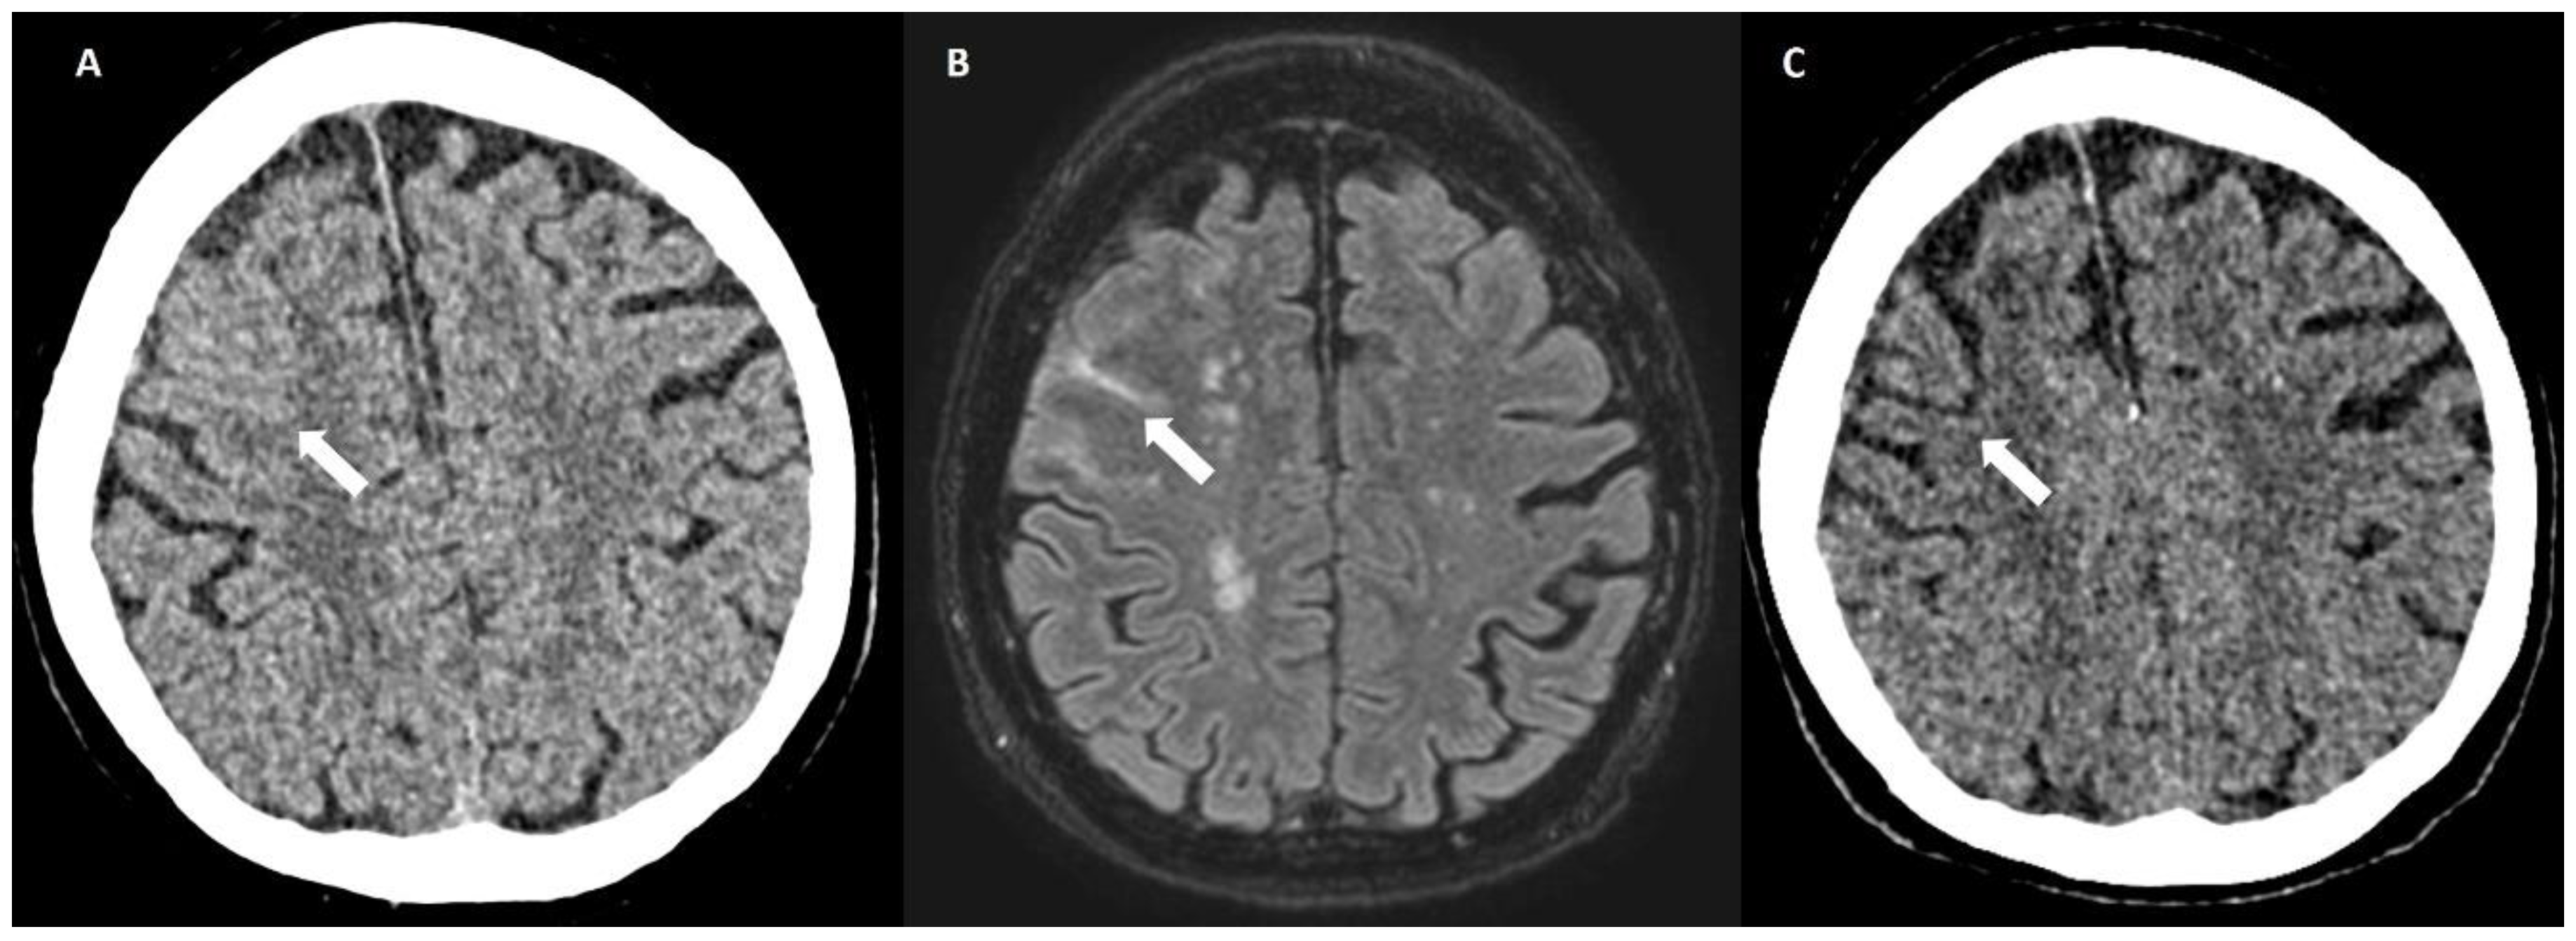

5.2.1. Enlarged Perivascular Spaces

6.4. Lobar Lacunes

6.5. Posterior White Matter Changes

6.6. Cortical Calcifications

- Baron, J.-C.; Jensen-Kondering, U.; Sacco, S.; Posener, S.; Benzakoun, J.; Pallud, J.; Oppenheim, C.; Varlet, P.; Turc, G. Can novel CT-and MR-based neuroimaging biomarkers further improve the etiological diagnosis of lobar intra-cerebral hemorrhage? J. Neurol. 2023, 270, 582–588. [Google Scholar] [CrossRef]